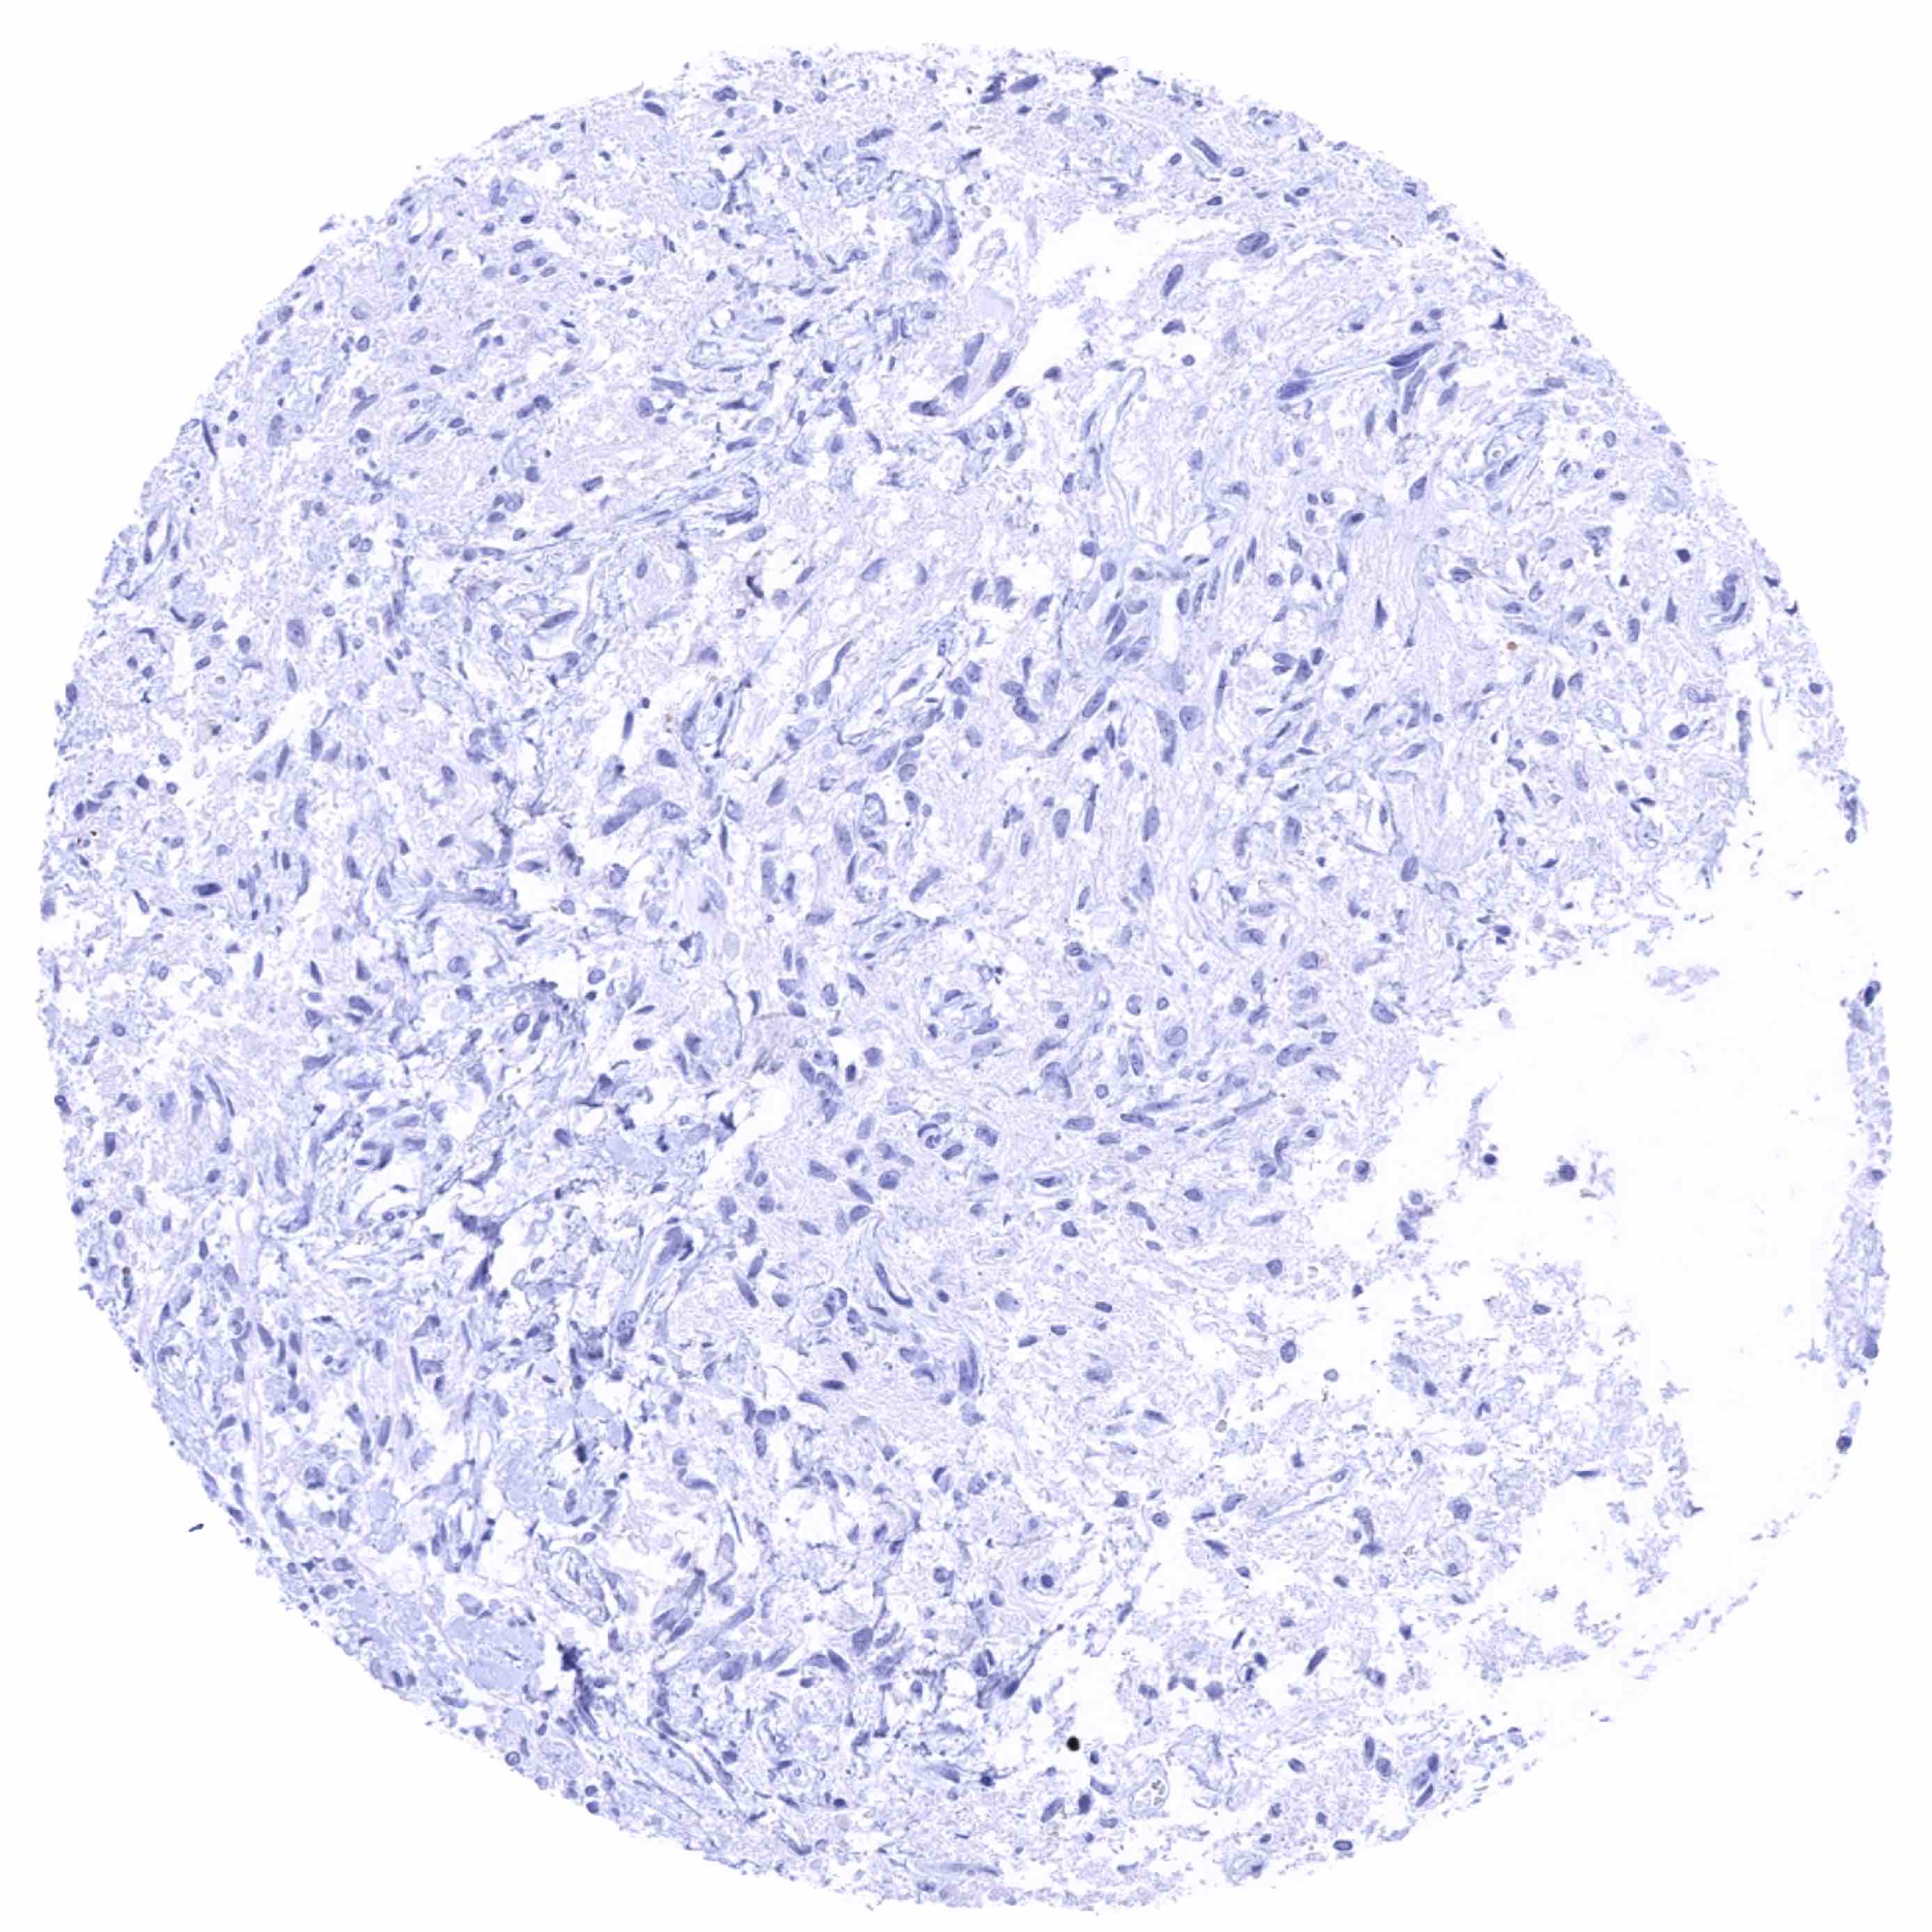

Adrenal gland

Aorta, media

Appendix, mucosa

Appendix, muscular wall

Bone marrow

Breast